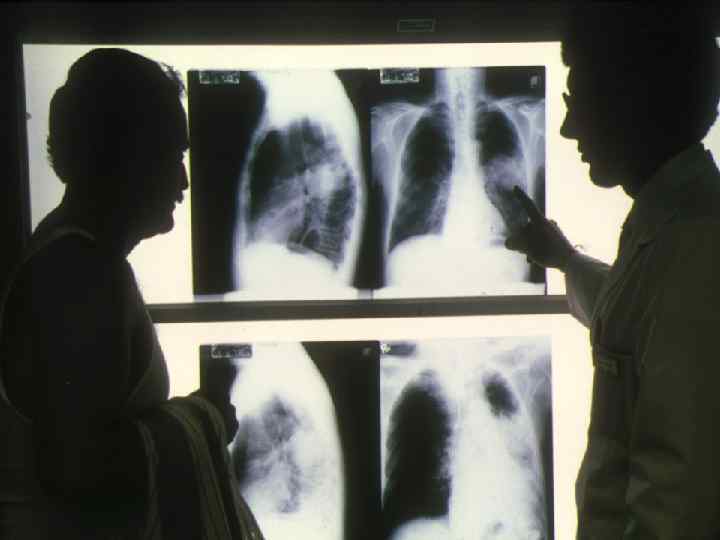

Рак легкого Симптомы: - Постоянный, мучительный кашель, кровохарканье. - Повторные пневмония, бронхит или боль в груди. Примерно в 85% случаев рака легкого, возникающих за год, можно обнаружить связь с курением. У людей, выкуривающих по две или больше пачек сигарет в день в течение 20 лет риск рака легкого повышен на 60— 70% по сравнению с некурящими. На рентгеновском снимке в легком видно патологическое объемное образование (стрелка). Позже при биопсии доказано, что это рак легкого.

Легкое здорового человека

Легкое курильщика

Рак легких